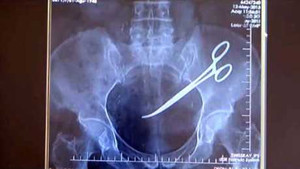

Bệnh viện Đa khoa tỉnh Bắc Kạn đang tiến hành xác minh việc bác sĩ phẫu thuật để quên chiếc kéo dài 15cm trong ổ bụng bệnh nhân từ 18 năm trước.